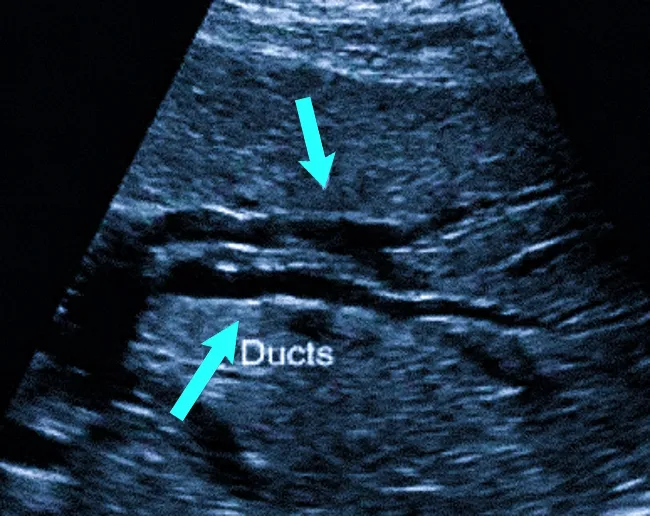

- ультразвуковая диагностика;

Наиболее часто для диагностики заболеваний желчевыводящих путей применяется ультразвуковое исследование.

Ультразвуковое обследование обычно предшествует более сложным методам диагностики. Оно позволяет обнаружить желчные камни и другие патологии. Внутреннее ультразвуковое исследование дает возможность проводить детальный осмотр желчевыводящих путей.